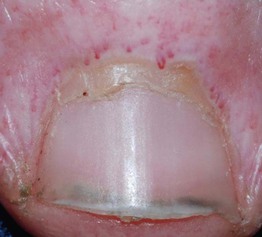

• Distal nail plate detachment, causing nail to look white to yellow-white (Fig. 58.2).

Fig. 58.2 Causes of onycholysis. *Due to secondary colonization with Pseudomonas aeruginosa. SCC, squamous cell carcinoma; TFTs, thyroid function tests.

• Chronic exposure to water and irritants (e.g. soaps) is a common cause.

• Associated with psoriasis, onychomycosis, hyperthyroidism, and medications (Table 58.2).